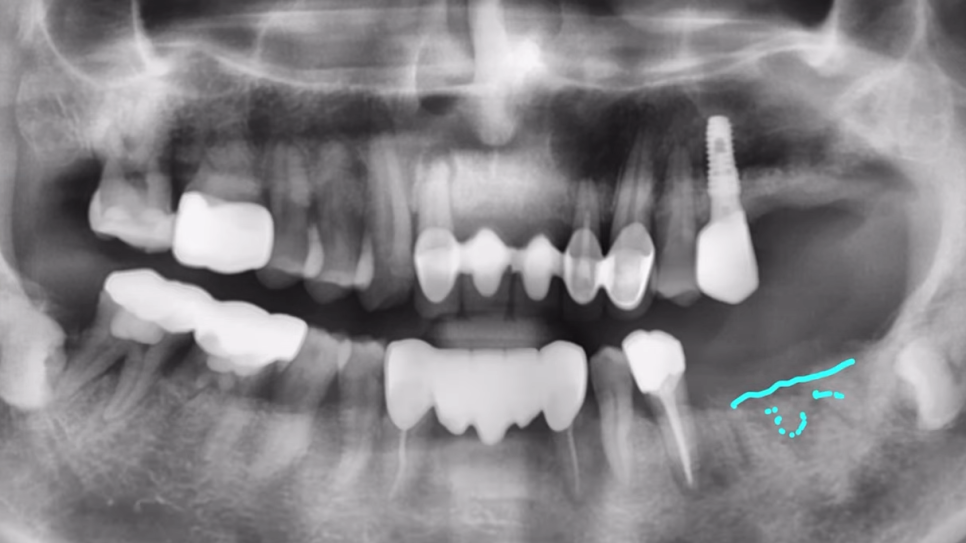

임플란트 식립 이후 뼈도 잘 차오르고, 예후도 좋은 모습을 볼 수 있습니다.

위처럼 염증이 심하거나, 뼈가 많이 소실된 경우라면

즉시 식립은 피하고, 뼈를 두둑하게 만들어 주는 뼈 이식부터 진행하는 게 좋은데요.

이렇게 뼈이식을 진행해,

이식한 뼈가 평탄하게 잘 안정화된 이후에 임플란트수술해야 더 안전합니다.

성공 가능성도 훨씬 높아지고요.